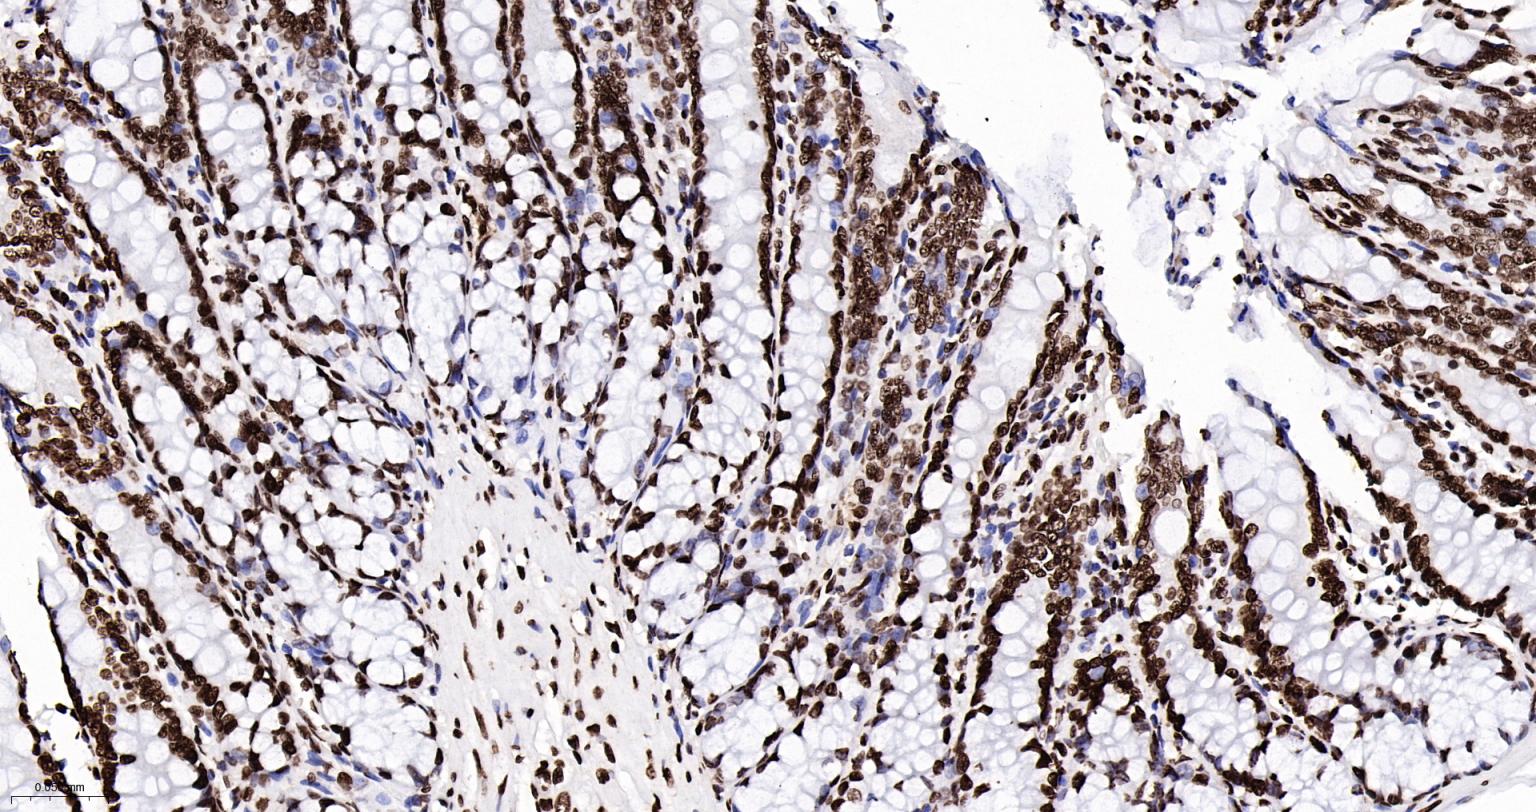

Paraformaldehyde-fixed, paraffin embedded Mouse Testicles; Antigen retrieval by boiling in sodium citrate buffer (pH6.0) for 15 min; Antibody incubation with Histone H2A.X Monoclonal Antibody, Unconjugated(bsm-61080R) at 1:200 overnight at 4°C, followed by conjugation to the SP Kit(Rabbit, SP-0023) and DAB (C-0010) staining.

Paraformaldehyde-fixed, paraffin embedded Rat Testicles; Antigen retrieval by boiling in sodium citrate buffer (pH6.0) for 15 min; Antibody incubation with Histone H2A.X Monoclonal Antibody, Unconjugated(bsm-61080R) at 1:200 overnight at 4°C, followed by conjugation to the SP Kit(Rabbit, SP-0023) and DAB (C-0010) staining.